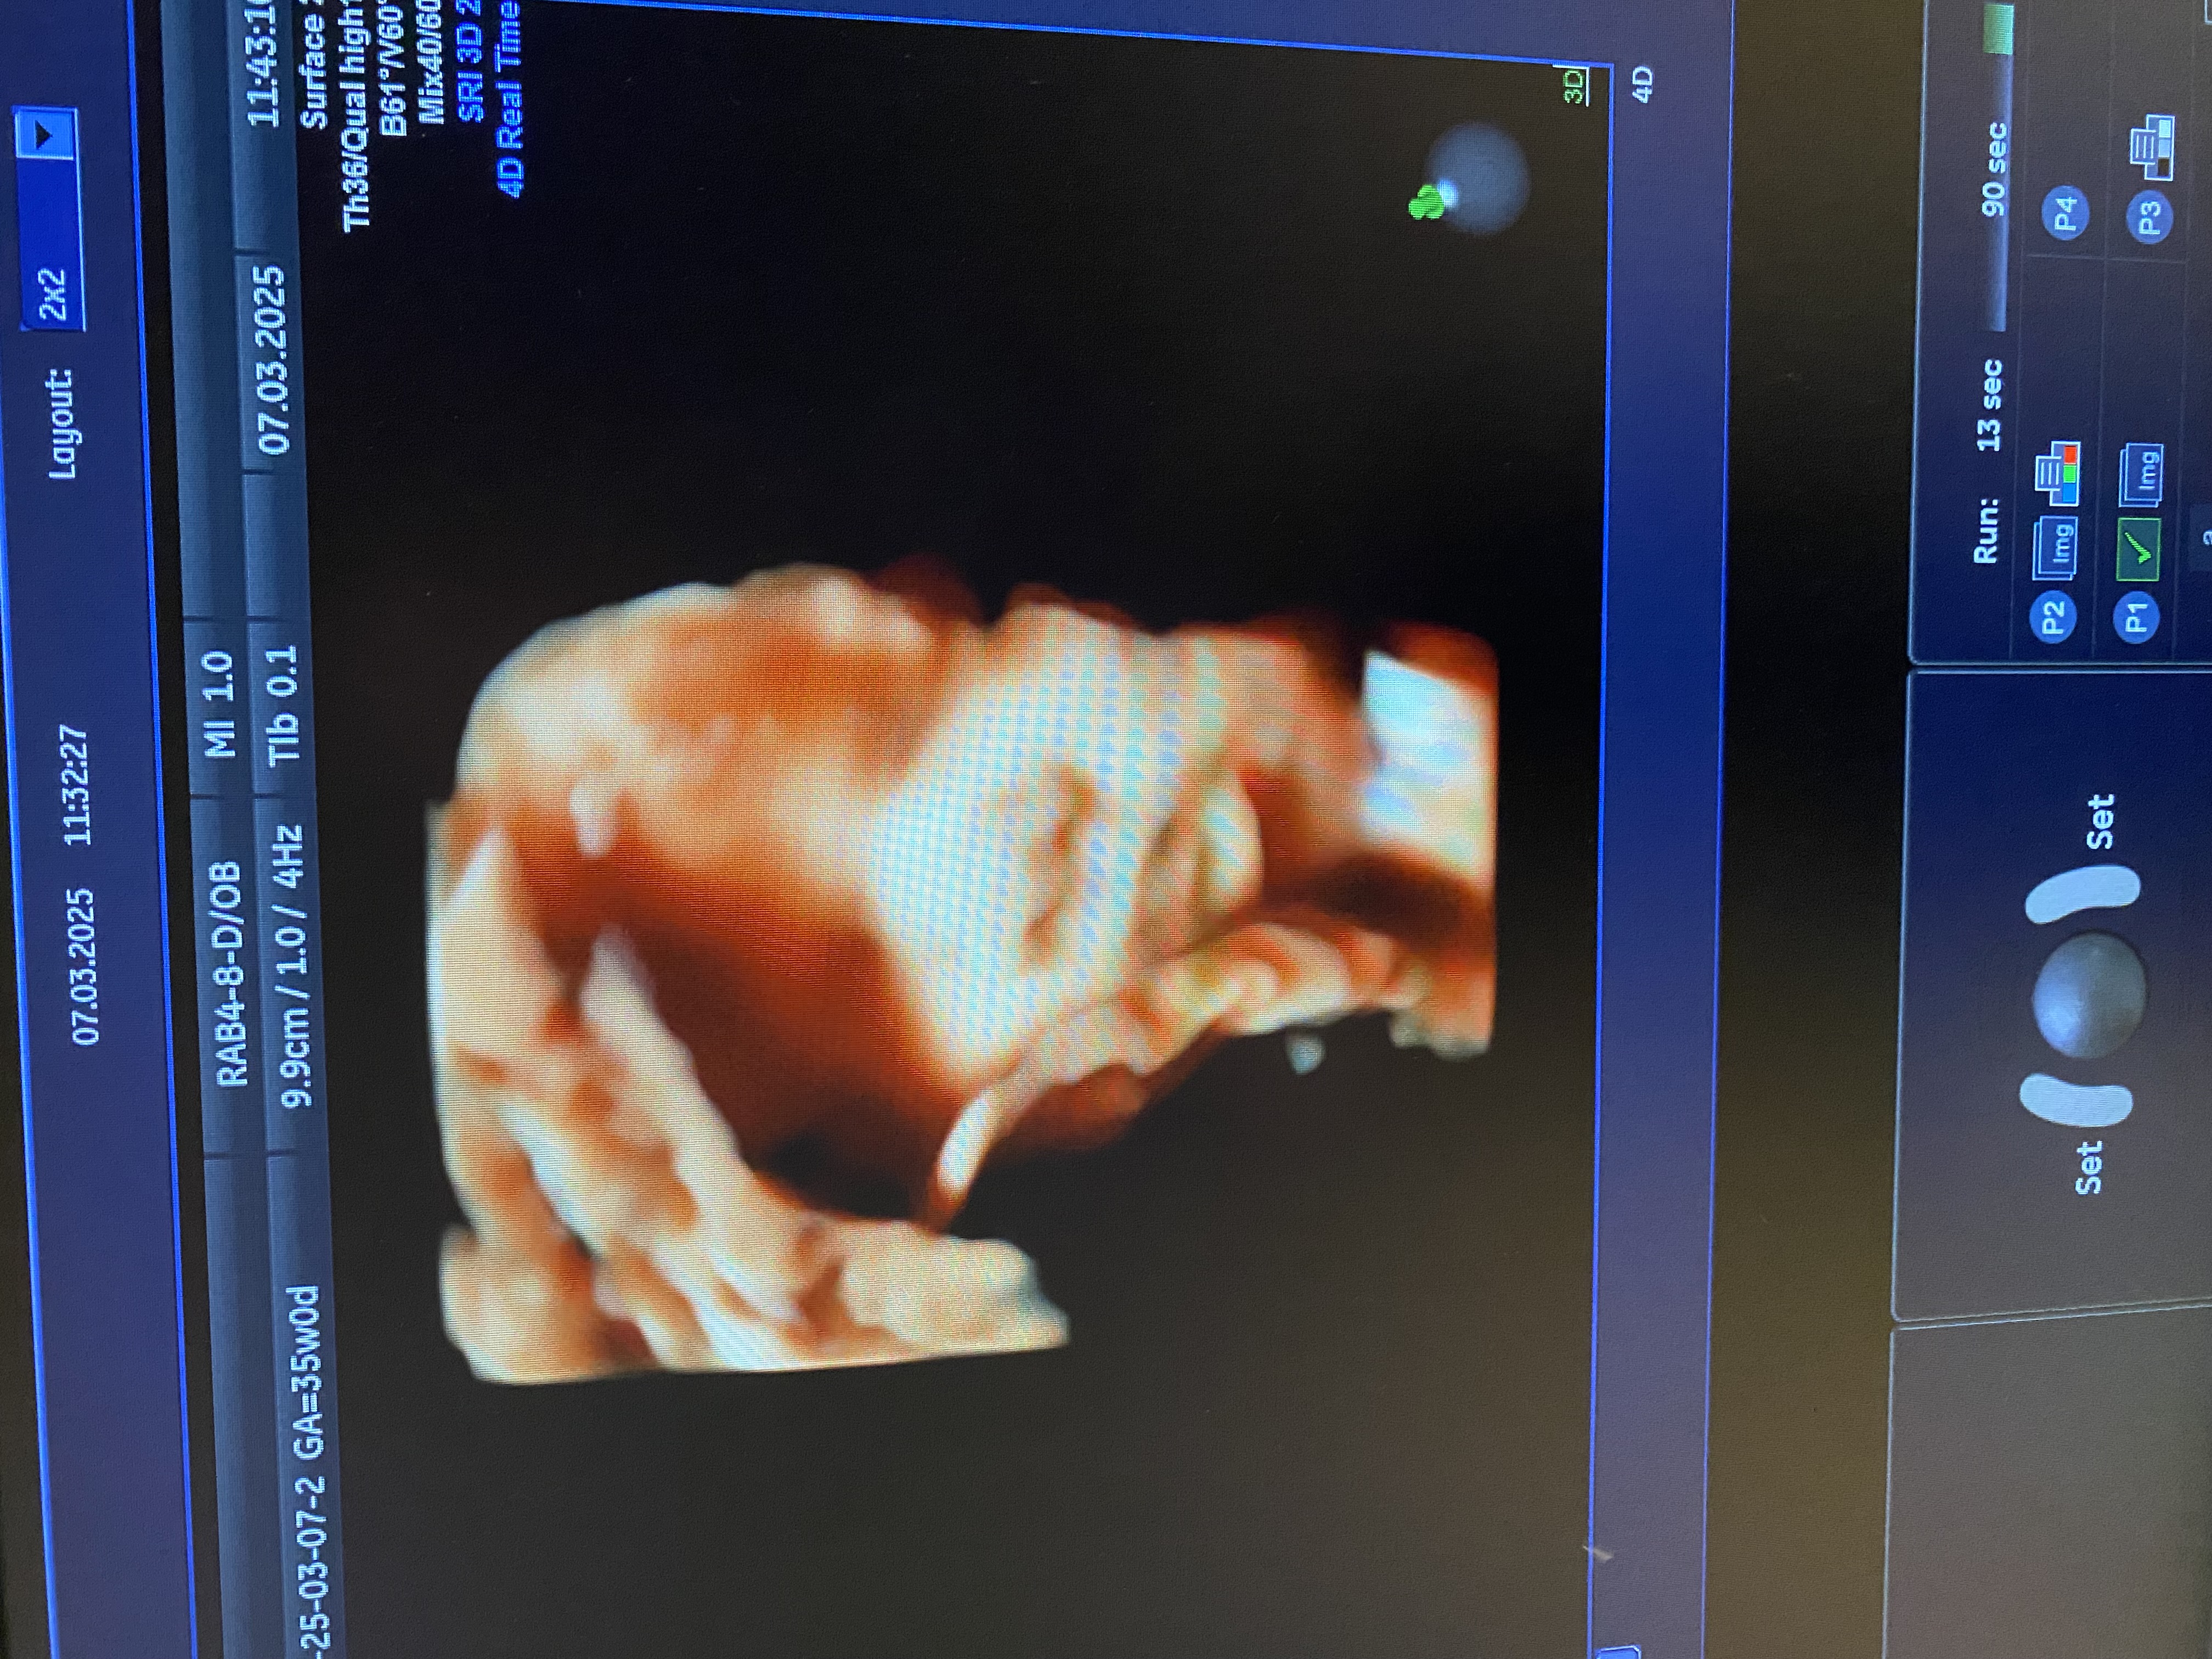

УЗИ. 35 недель и 4 дня

УЗИ, КТГ, доплерКакая она уже большая ☺️🥹. Вес 2570 грамм.

Это было первое УЗИ, на котором я уже перестала понимать где и что находится, такая она большая, разглядела только пальцы и голову😅

Когда я была беременна сыном, у нас было только черно белое узи. Помню как мы с мужем вертели фото сына пытаясь понять на кого он будет похож. У вас такое шикарное цветное фото! Можно начать знакомиться уже представляя внешность доченьки. Можно взять свои детские фото и фото мужа и поискать общие черты. В общем простор для творчества просто небывалый.